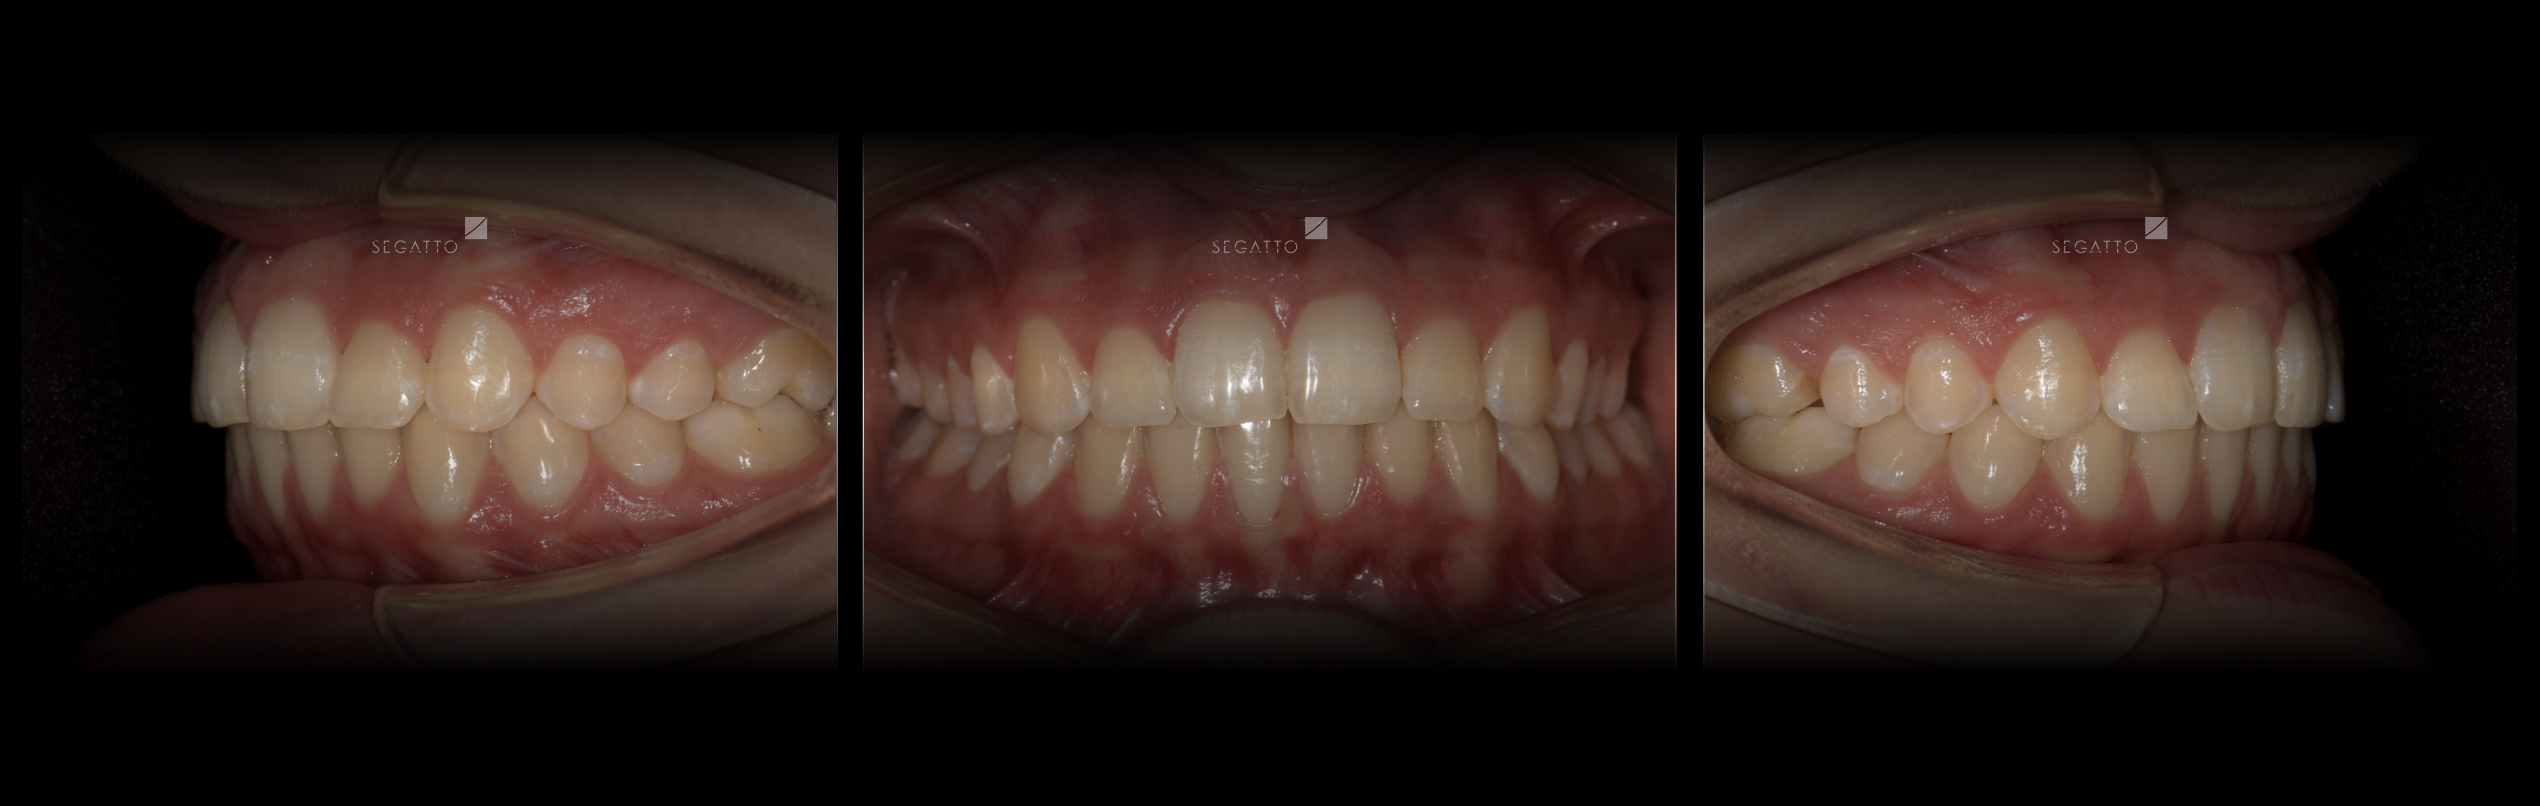

Orthodontics

Cases